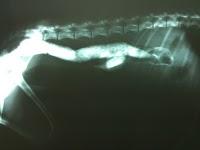

En primer lugar pediros disculpa a todos los seguidores por este lapsus en aportaros post, pero hemos tenido unas semanas de mucho trabajo y estudios sin dejarnos tiempo apenas para nada. Este pequeño artículo os quiero hacer referencia a dos caso clínico que he tenido esta semana y me han parecido interesante por su frecuencia en el tiempo. Con la llegada del calor , acudimos a la playa con nuestros perros antes de que se habrá la temporada de playa y lo prohiban o bien en calas que está permitida la entrada a mascotas. pues estos caso que hemos visto en la clínica no es por golpe de calor, es por una serie de trastornos intestinales por comer arena, en un caso por ser cachorro y le atraía el sabor de la arena y en otro que sus propietarios le lanzaban "restos de comida" que al contacto con la arena se mezclaba y zas, al estómago. Las consecuencias menos graves sería vómitos y decaimiento, en el peor de los casos una parálisis intestinal, podría incluso producirse una intususcepción, porción de intestino que se solapa con la anterior, provocando una parálisis e impidiendo el paso de alimentos . Os pongo una radiografía donde se aprecia perfectamente el asa intestinal con la misma densidad de un hueso, es decir , "mazizo" , lleno de arena que al fin y al cabo son muchas piedras de diminut tamaño. A parte del vómito tenia dolor abdominal, le cambiamos la dieta a muy fibrosa, laxante vía oral y vía rectal, en 24 horas defecó y mejoro enormemente su estado.La llegada del buen tiempo